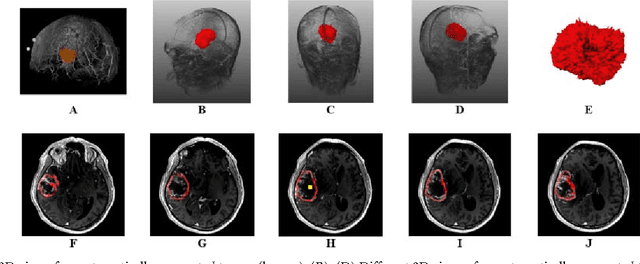

Abstract:Volumetric change in glioblastoma multiforme (GBM) over time is a critical factor in treatment decisions. Typically, the tumor volume is computed on a slice-by-slice basis using MRI scans obtained at regular intervals. (3D)Slicer - a free platform for biomedical research - provides an alternative to this manual slice-by-slice segmentation process, which is significantly faster and requires less user interaction. In this study, 4 physicians segmented GBMs in 10 patients, once using the competitive region-growing based GrowCut segmentation module of Slicer, and once purely by drawing boundaries completely manually on a slice-by-slice basis. Furthermore, we provide a variability analysis for three physicians for 12 GBMs. The time required for GrowCut segmentation was on an average 61% of the time required for a pure manual segmentation. A comparison of Slicer-based segmentation with manual slice-by-slice segmentation resulted in a Dice Similarity Coefficient of 88.43 +/- 5.23% and a Hausdorff Distance of 2.32 +/- 5.23 mm.